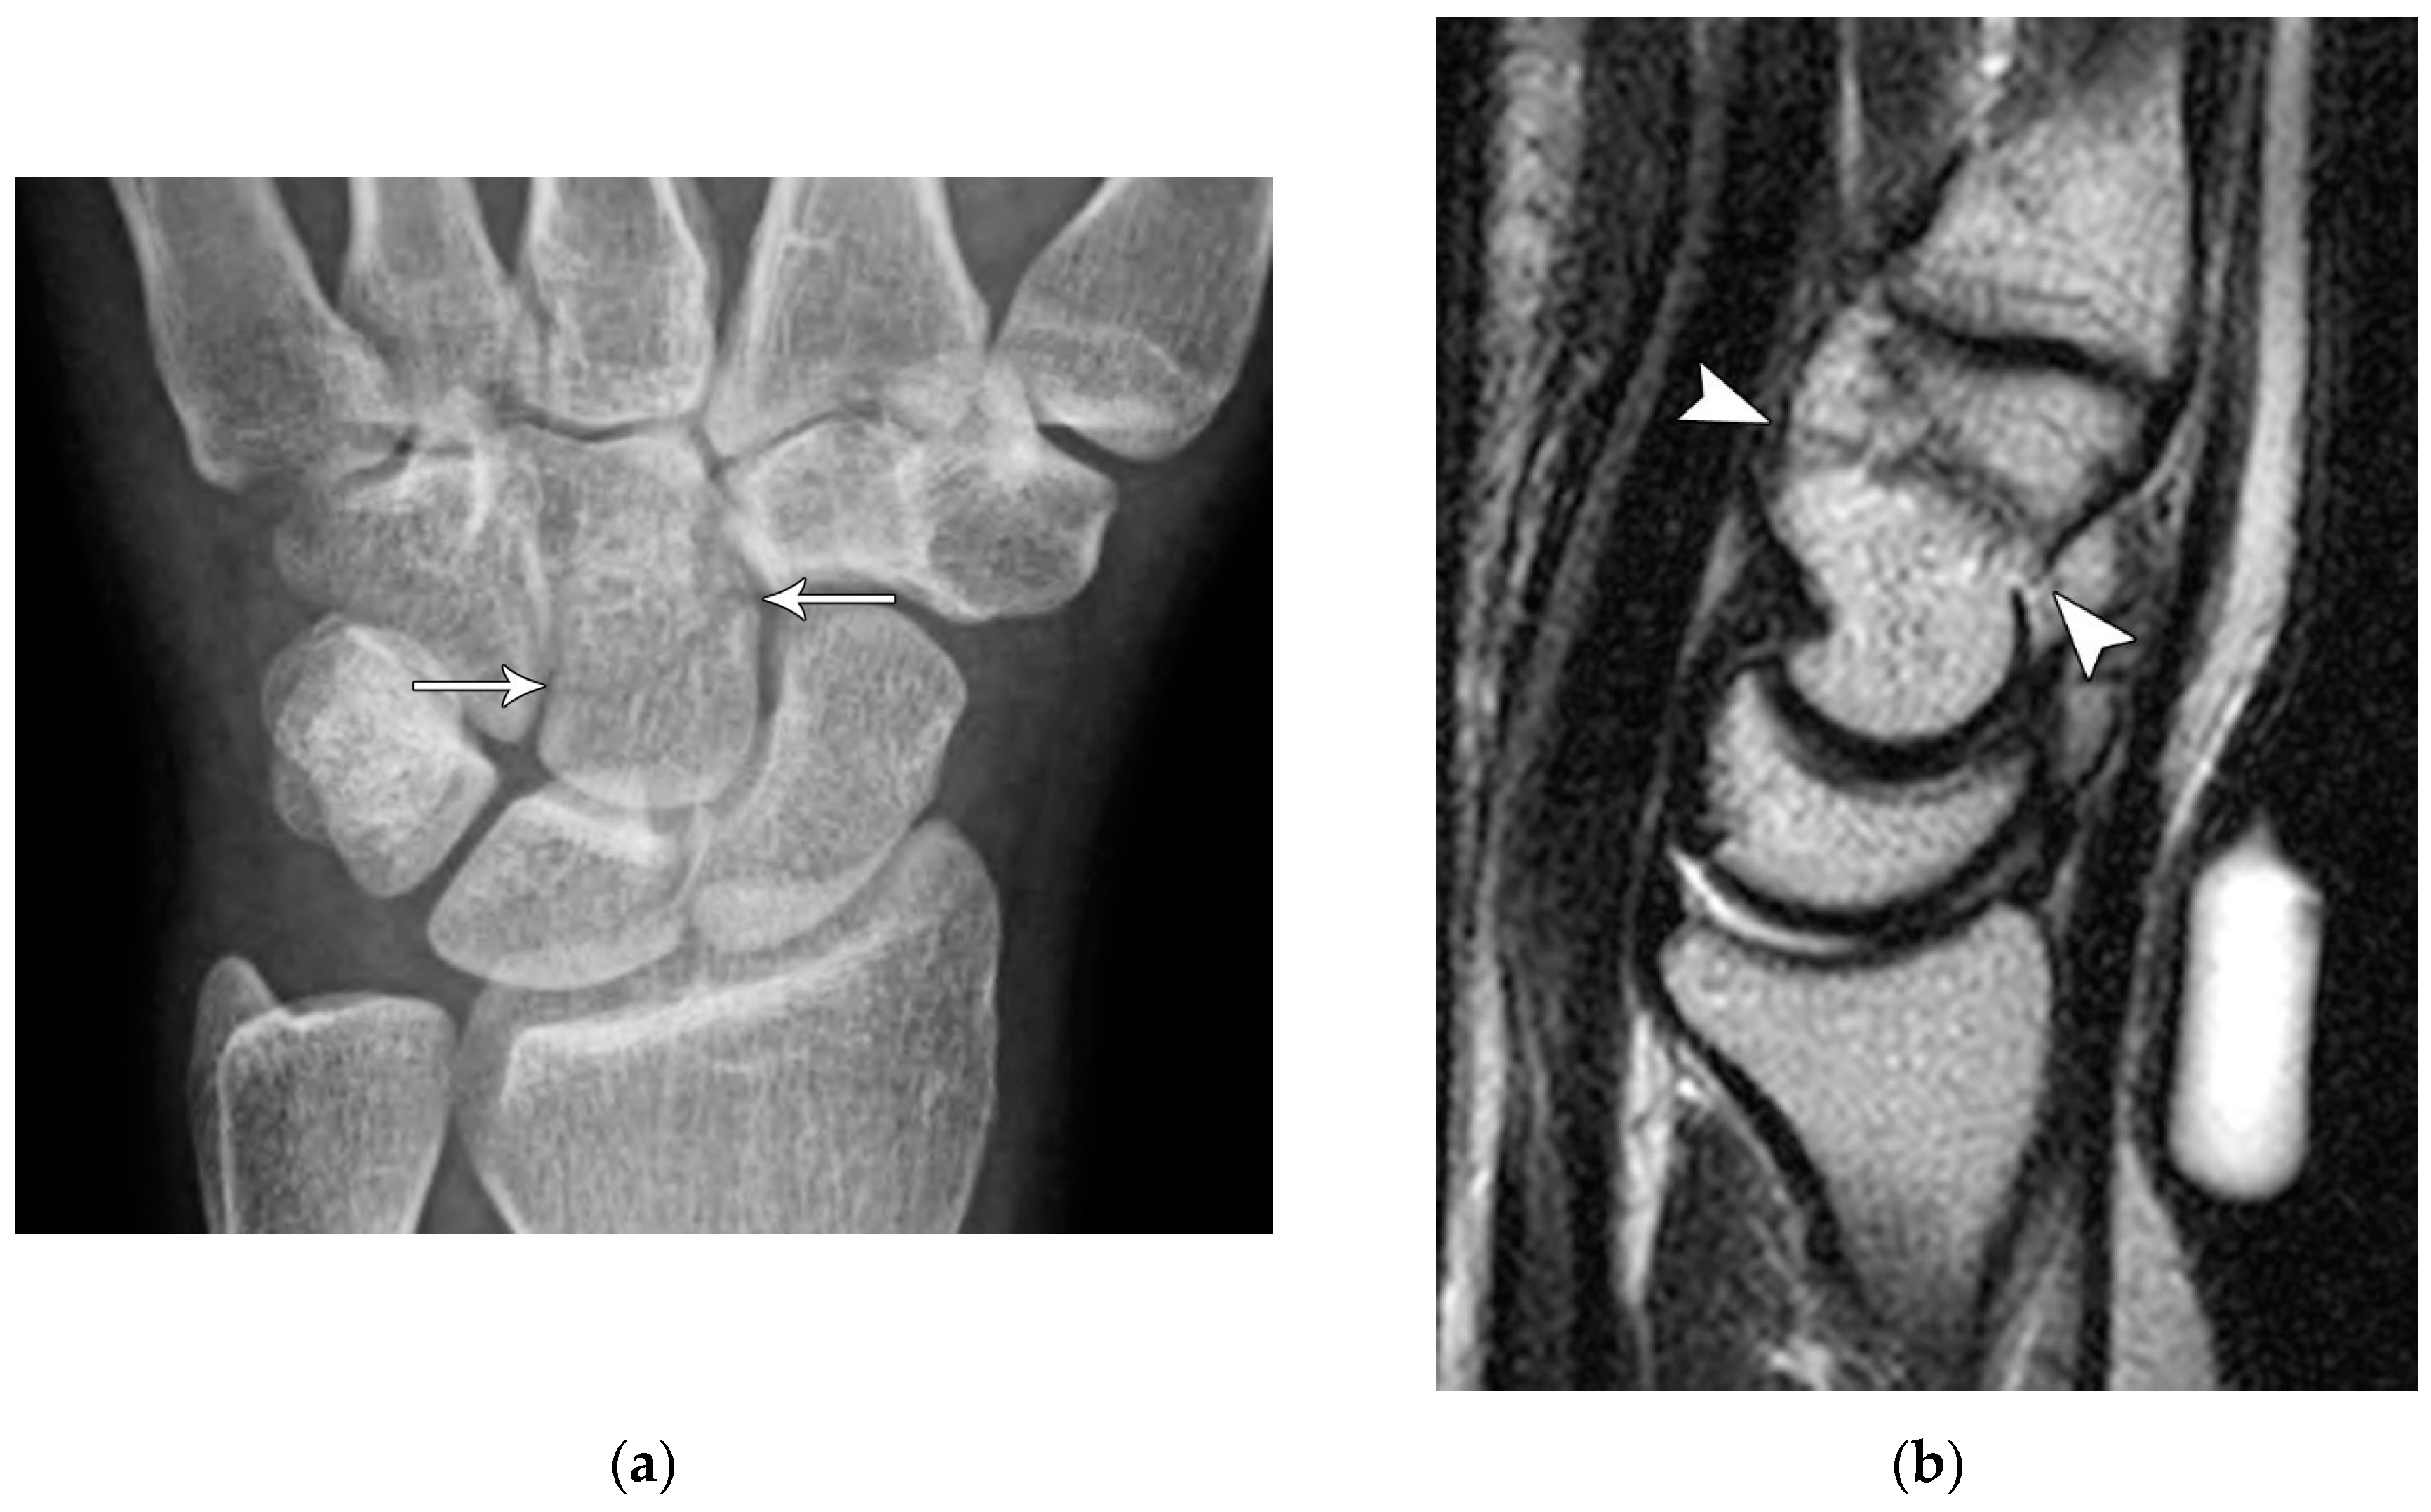

Figure 5. (a) PA radiograph showing marked sclerosis (arrow) of the proximal pole of the scaphoid after a scaphoid fracture. (b) Coronal reformatted CT in a different patient showing sclerosis (arrow) of the proximal pole of the scaphoid after a scaphoid fracture, indicating osteonecrosis.